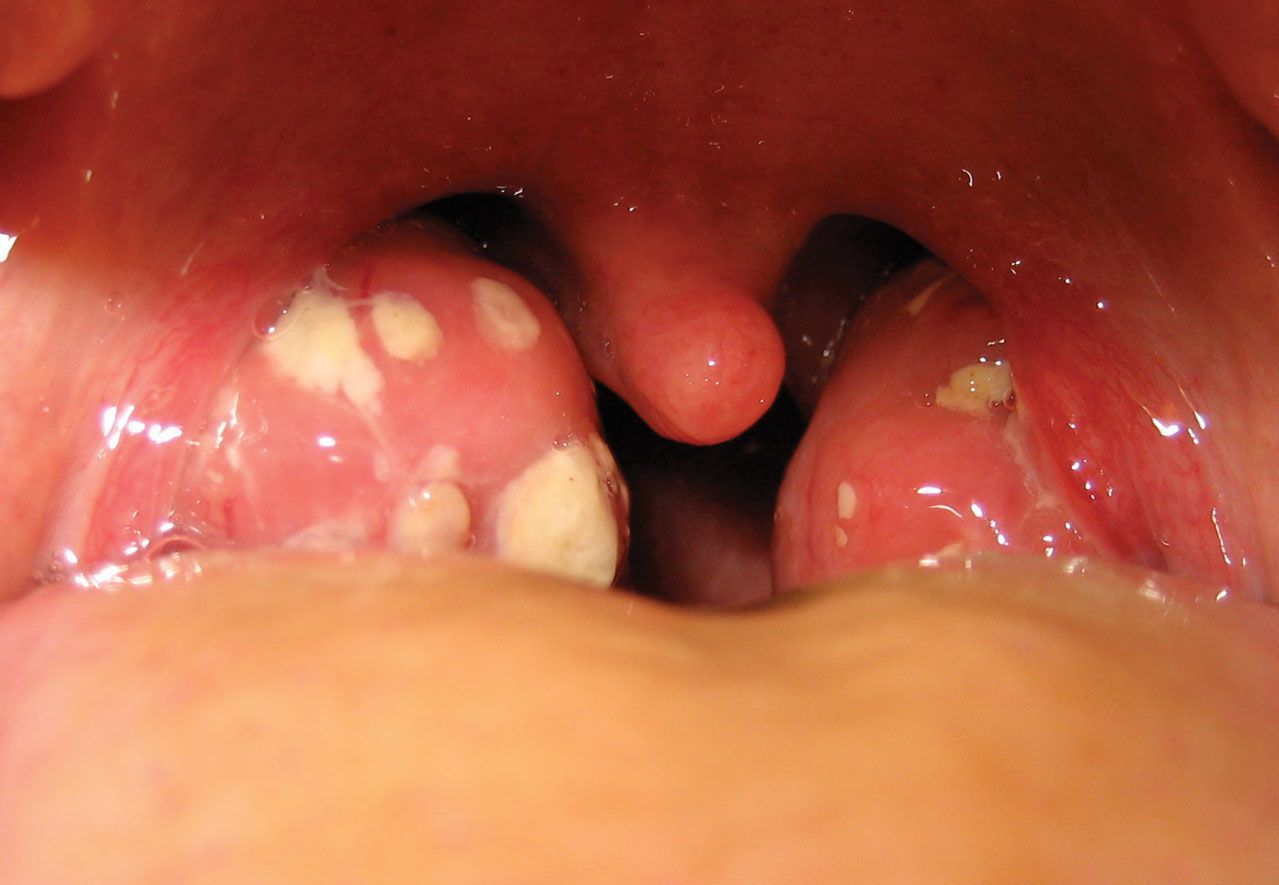

Tonsillitis is inflammation of the tonsils, two oval-shaped pads of tissue at the back of the throat — one tonsil on each side. Signs and symptoms of tonsillitis include swollen tonsils, sore throat, difficulty swallowing and tender lymph nodes on the sides of the neck.